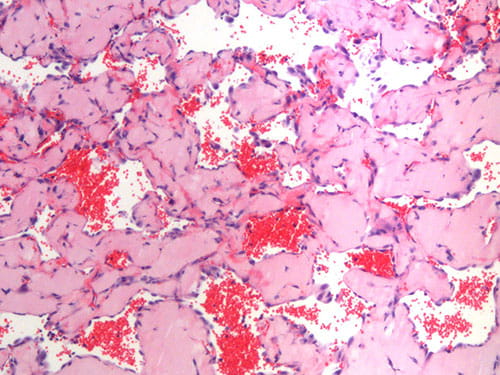

1) Diagnostic biomarker identification and analysis for vascular anomalies

2) Human patient-derived cell xenograft models of vascular anomalies

3) Mouse models of vascular anomalies

“Pathogenesis and Treatment of Kaposiform Lymphangiomatosis“

The major goals of this project are to test the hypothesis that the somatic p.Q61R NRAS mutation in human endothelial cells drives the pathogenesis of KLA and elevated production of ANGPT2.